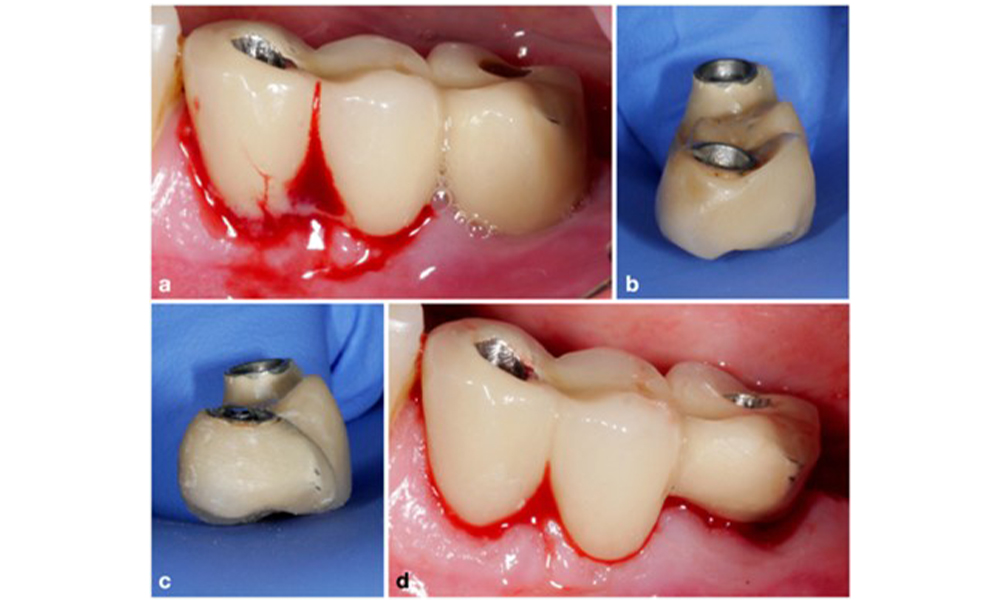

Since the primary etiologic factor for peri-implant biological complications is the oral biofilm, two crucial aspects should always be considered as integral part of the treatment independent of a diagnosis of peri-implant mucositis or peri-implantitis: (1) the level of oral hygiene, and (2) the cleanability of the prosthetic restoration (figure 4).

Thus, both the patient's oral hygiene routines and the prosthetic restoration’s design and implant positioning should support effective cleaning. If required, adjustments to the existing restoration (figure 5) and specific instructions for tailored oral hygiene measures are essential (figure 6) (Hamilton et al. 2023; Jepsen et al. 2015).

The prosthetic restoration should be removed during both non-surgical and surgical treatment to improve access to the implant surface. The choice of surgical intervention (e.g., resective, reconstructive, or combined) depends on several factors: (1) defect morphology (e.g., horizontal, dehiscence, intra-osseous, or combined) (figure 10), (2) implant surface (i.e., turned or modified/”rough”), and (3) presence or absence of sufficient keratinised and attached mucosa.